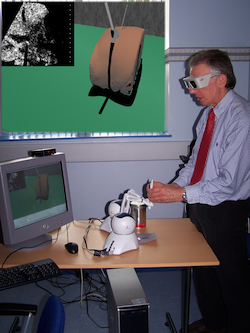

F. P. Vidal, N. W. John, D. A. Gould, and A. E. Healey.

F. P. Vidal, N. W. John, D. A. Gould, and A. E. Healey.

We present an integrated system for training visceral needle puncture procedures. Our aim is to provide a cost effective and validated training tool that uses actual patient data to enable interventional radiology trainees to learn how to carry out image-guided needle puncture. The input data required is a computed tomography scan of the patient that is used to create the patient specific models. Force measurements have been made on real tissue and the resulting data is incorporated into the simulator. Respiration and soft tissue deformations are also carried out to further improve the fidelity of the simulator. Keywords: Physically based modelling, Virtual reality |

Developing an immersive ultrasound guided needle puncture simulator.

We present an integrated system for training ultrasound guided needle puncture. Our aim is to provide a cost effective and validated training tool that uses actual patient data to enable interventional radiology trainees to learn how to carry out image-guided needle puncture. The input data required is a computed tomography scan of the patient that is used to create the patient specific models. Force measurements have been made on real tissue and the resulting data is incorporated into the simulator. Respiration and soft tissue deformations are also carried out to further improve the fidelity of the simulator. Keywords: image guided needle puncture training, interventional radiology training, needle puncture |

We present a simulator for guided needle puncture procedures. Our aim is to provide an effective training tool for students in interventional radiology (IR) using actual patient data and force feedback within an immersive virtual environment (VE). Training of the visual and motor skills required in IR is an apprenticeship which still consists of close supervision using the model: (i) see one, (ii) do one, and (iii) teach one. Training in patients not only has discomfort associated with it, but provides limited access to training scenarios, and makes it difficult to train in a time efficient manner. Currently, the majority of commercial products implementing a medical VE still focus on laparoscopy where eye-hand coordination and sensation are key issues. IR procedures, however, are far more reliant on the sense of touch. Needle guidance using ultrasound or computed tomography (CT) images is also widely used. Both of these are areas that have not been fully addressed by other medical VEs. This paper provides details of how we are developing an effective needle guidance simulator. The project is a multi-disciplinary collaboration involving practising interventional radiologists and computer scientists. Keywords: Interventional radiology; Virtual environments; Needle puncture; Haptics |